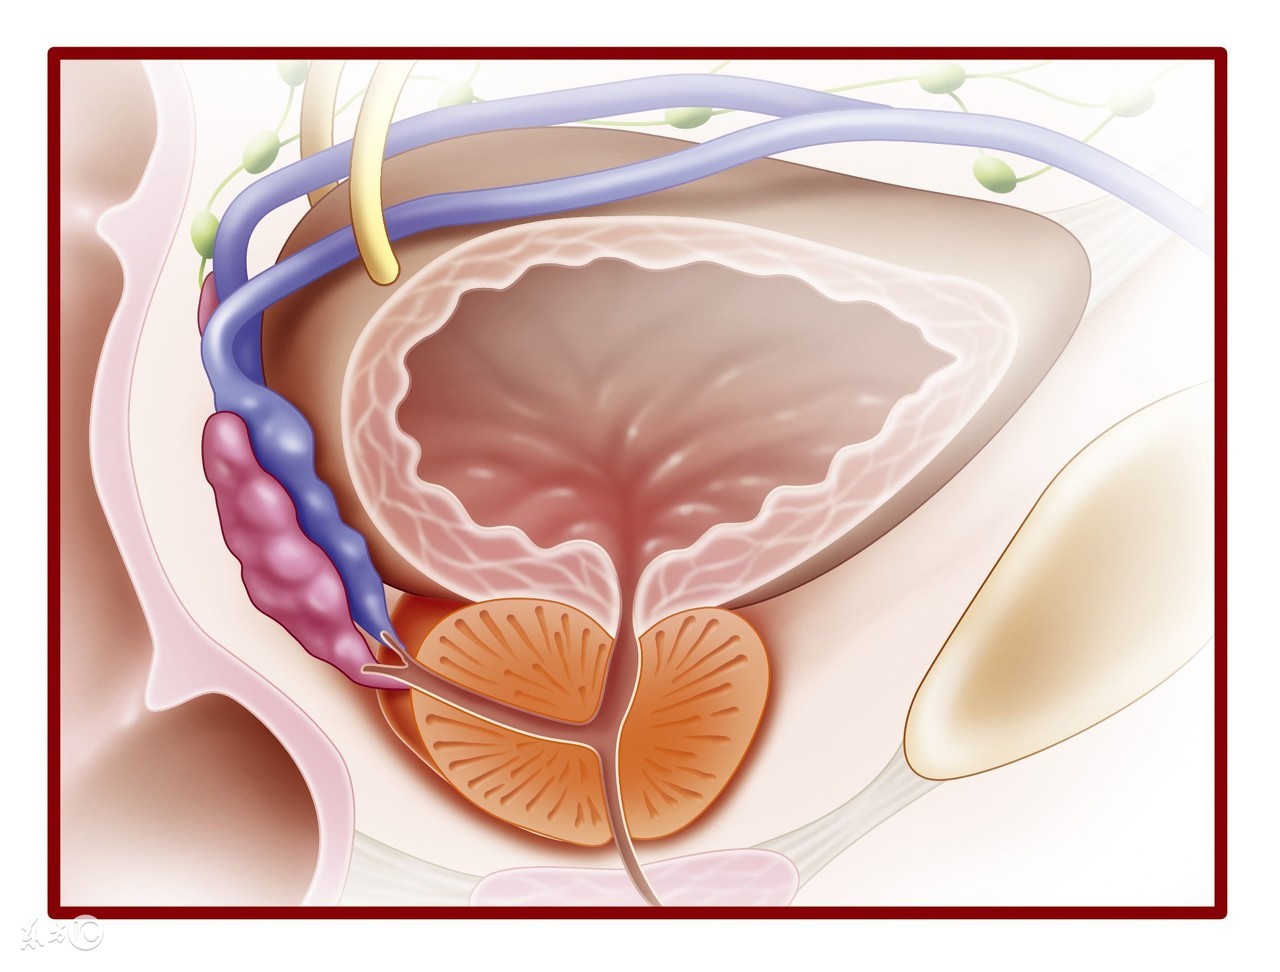

病因 膀胱属腹膜间位器官, 膀胱空虚时深藏骨盆内, 四周有骨盆保护, 一般不易受伤。腹膜外型膀胱破裂常由于外力伤及膀胱前下壁所致, 当膀胱充盈变薄时高出耻骨联合上的膀胱顶部及后壁受到*力暴**伤可导致腹膜内型膀胱破裂。所受*力暴**伤如车祸、撞击伤、挤压伤, 部分伴骨盆骨折;医源性损伤见于内腔镜操作、盆腔手术误伤等, 自发性破裂多见于醉酒后膀胱破裂、病变膀胱(如膀胱结核或肿瘤)过度充盈、前列腺肥大、尿潴留过度引起。